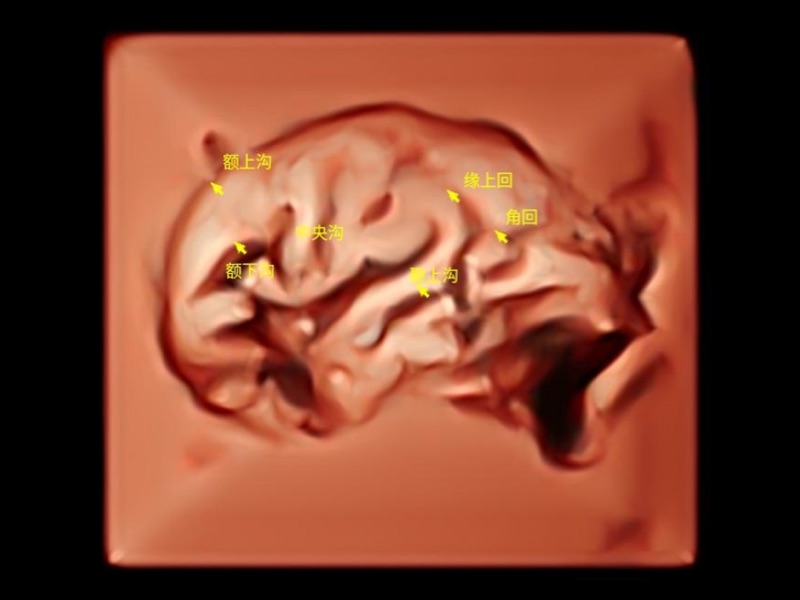

独有场成像发射技术

自适应聚合重建技术

独家XPUs混合硬件架构